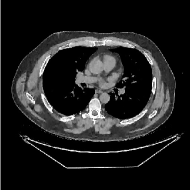

III-B3 Generalization Capability Comparisons between a “Denoising” Deep NN and the Proposed PWLS-ST- Method

This section compares the generalization capabilities between the proposed MBIR method, PWLS-ST-, and a denoising deep NN, FBPConvNet [14], that are trained from the phantom data; in particular, we tested the trained PWLS-ST- and FBPConvNet models to phantom and clinical scan data. The results in Fig. 6 show that the non-MBIR FBPConvNet method has higher overfitting risks, compared to the proposed PWLS-ST- MBIR method. When tested on clinical scan data, PWLS-ST- achieves much more accurate reconstruction, compared to FBPConvNet. See Fig. 6(b). When tested on phantom data, FBPConvNet generates more unnatural features as the number of views reduces, although it gives lower RMSE values compared to PWLS-ST-. See zoom-ins in Fig. 6(a). The FBPConvNet results above correspond to those in the recent work [16] that FBPConvNet [14] generated some unexpected structures.